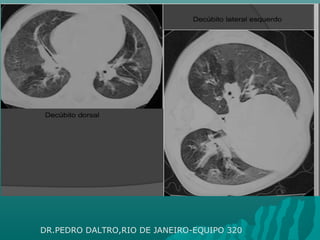

 TOMOGRAFIA CON CORTES ESPIRATORIOS :TOMOGRAFIA CON CORTES ESPIRATORIOS :

En posición decúbito supino en niños que cooperan con unaEn posición decúbito supino en niños que cooperan con una

espiración forzada. Se realizan 3 cortes espiratorios: a nivelespiración forzada. Se realizan 3 cortes espiratorios: a nivel

superior, medio e inferior, para obtener adecuada valoración de cadasuperior, medio e inferior, para obtener adecuada valoración de cada

pulmón tanto en inspiración como en espiraciónpulmón tanto en inspiración como en espiración

En niños pequeños que no cooperan con la respiración se realiza enEn niños pequeños que no cooperan con la respiración se realiza en

decúbito lateral o prono, permitiendo obtener adecuada valoracióndecúbito lateral o prono, permitiendo obtener adecuada valoración

de los segmentos posteriores de ambos campos pulmonares.de los segmentos posteriores de ambos campos pulmonares.

DR. PEDRO DALTRO ,RIO DE JANEIRO , EQUIPO 320

DR.PEDRO DALTRO,RIO DE JANEIRO-EQUIPO 320